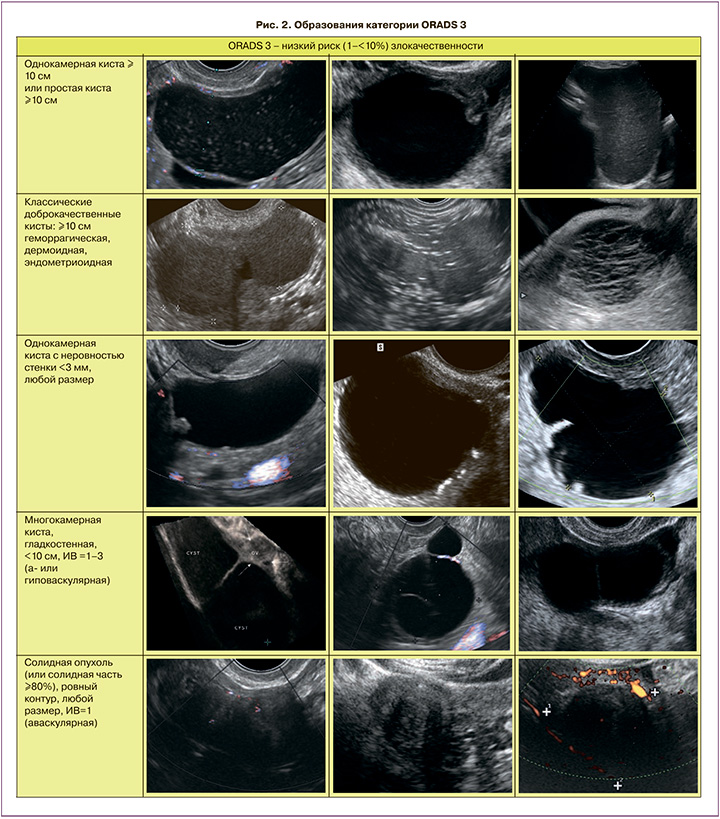

ORADS 3

ORADS 3 – категория низкого риска (от 1% до 10%) злокачественности, включает более крупные образования доброкачественной категории и другие поражения с более высоким риском злокачественности. В нее включены простые кисты; односторонние гладкие несимметричные кисты; образования с классическими доброкачественными признаками, размеры которых превышают или равны 10 см. Уровень отсечения в 10 см был использован с учетом значительного увеличения риска развития злокачественных новообразований, с использованием данных IOTA 1–3 [10, 14–19]. Также в эту категорию входят однокамерные кисты с неровностью внутреннего контура стенки; многокамерные кисты менее 10 см без папиллярного компонента (-ов) с ИВ менее 4; а также аваскулярные солидные опухоли с ровным внешним контуром любого размера (подразумеваются фибромы) (рис. 2). Начиная с категории ORADS 3, оценка васкуляризации включается в систему стратификации риска. Дескрипторы ORADS 3 перечислены в табл. 2.

В эту категорию отнесли те образования, которые не могут быть однозначно отнесены к доброкачественным, но и не имеют однозначно злокачественных признаков. Согласно данным AIUM, опубликованным в 2017 г., субъективная оценка категории образования врачом-экспертом УЗИ превосходит по информативности ROMA в группе сложных опухолей (чувствительность УЗИ – 96,7%) [20].

Однокамерные кисты с истинными перегородками должны оцениваться с учетом количества, толщины и «регулярности» перегородок. Если имеется одинарная тонкая (3 мм) перегородка, то, скорее всего, образование будет доброкачественным [21]. В скрининговом исследовании, в котором оценивались 2870 кист с 1 или более перегородкой, без папиллярных разрастаний, большинство кист оказались серозными или муцинозными цистаденомами, 1 – пограничной опухолью, с отсутствием рака яичников. Это позволяет предположить, что многокамерные кисты с малым числом тонких перегородок без папиллярных разрастаний и солидных компонентов ассоциированы с очень низким риском злокачественности [21].

Размер опухоли является важным элементом оценки для определения риска злокачественности. Он должен быть получен путем измерения наибольшего диаметра независимо от плоскости, в которой этот диаметр измеряется. Зрелые тератомы и эндометриомы имеют низкий риск злокачественности, как правило, менее 0,8%, при небольших размерах [22]. Риск злокачественной трансформации повышается при больших эндометриомах (>9 см) и у женщин старше 45 лет [23]. Поэтому, как и в случае муцинозных кист, возможно динамическое наблюдение для оценки морфологических изменений, в частности, быстрого роста или появления солидных васкуляризированных компонентов.

Злокачественная трансформация муцинозной цистаденомы яичников возможна, но обычно в течение достаточно длительного периода. Согласно данным некоторых немногочисленных публикаций, считается, что пограничные муцинозные опухоли яичников встречаются при размерах более 10 см и с выраженной многокамерностью [24]. Таким образом, активно выжидательная тактика с ультразвуковым контролем еще возможна только при небольших кистах с меньшим количеством камер и отсутствием кровотока в них [25, 26]. Фибромы яичников с их классическими ультразвуковыми признаками – гипоэхогенное образование с акустическим затенением и отсутствием васкуляризации относятся к категории ORADS 3. Фибромы могут вызывать асцит и плевральный выпот, называемый синдромом Мейгса.